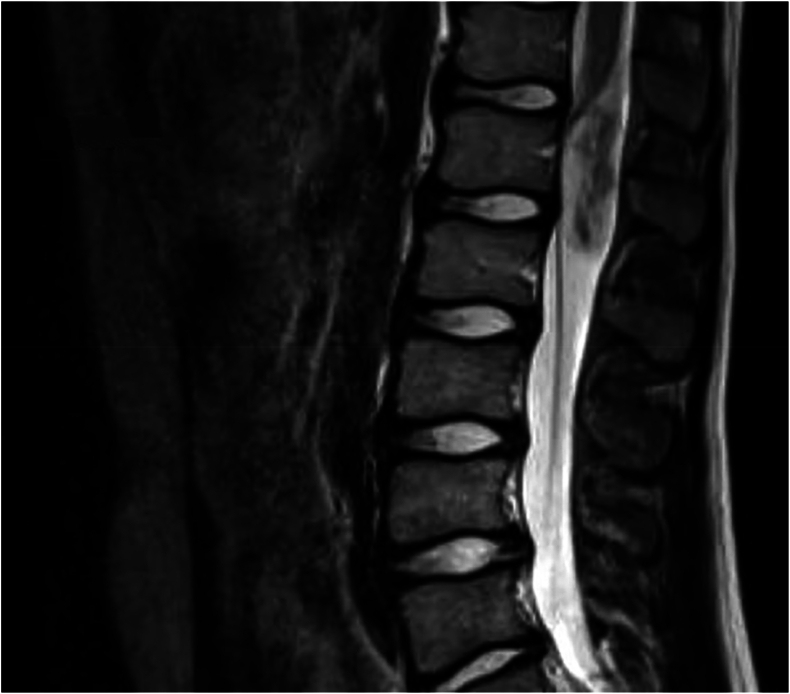

Results: The average age of the 1409 patients was 15.5 years (95% CI: 15.4, 15.6). Back pain (90.1%) was the most common reason for lumbar MRI. Thirty-five UFs were found in 33 patients (2.3%): 19 were spinal cord-related, 15 were peritoneal-related, and one was vascular. Eight peritoneal findings involved the kidneys: two atrophy, two hypoplasia, two renal cysts, one pelvic kidney, and one hydronephrosis. Five patients had a syrinx, and two had spine tumors. Out of 33 patients with UFs, 11 required a change in treatment plan (33.3%). Back pain was not associated with an increased risk of UF. Patients with an UF on MRI had 2.60 times higher odds of experiencing a change in treatment plan.

Abstract Image